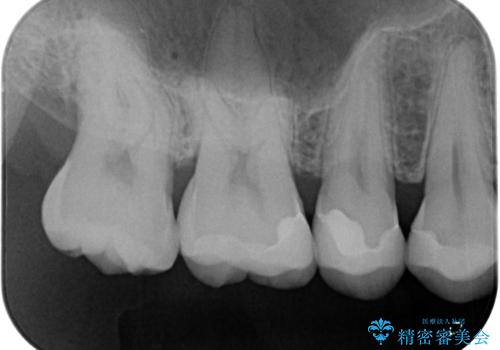

左上の奥歯は神経が失活しており、根管治療が必要な状態でした。

その他は銀歯のインレー(部分的な詰め物)が装着されており、それらはむし歯を除去した後にセラミックインレーにて修復治療を行い、左下と根管治療を行う左上の奥歯はオールセラミッククラウンにて補綴治療を行うこととしました。

根管治療の途中で、矯正治療の後戻りが気になるとのことで、下顎前歯の叢生を改善するためにマウスピース矯正を並行して行いました。